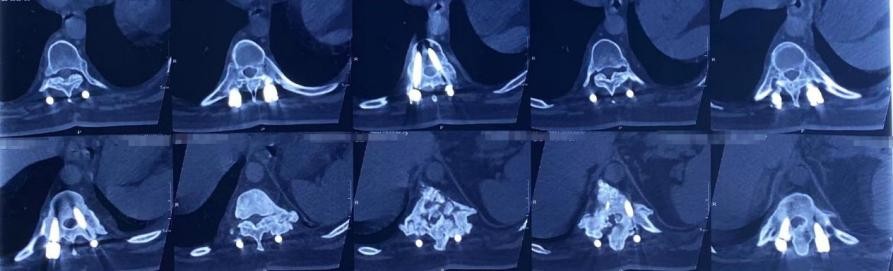

我仔细地观察了吴先生的影像学片子和其他检查单,并给他进行了详细地查体,怀疑他是强直性脊柱炎脊柱骨折。于是建议他进一步做相关检查,最后排除了肿瘤、结核可能,并发现他的HLA-B27呈阳性,X线显示两侧骶髂关节融合,符合强直性脊柱炎表现。而从他的影像学片子上可以观察到,胸11椎体出现溶骨性腔隙,脊髓已经受到压迫,考虑是强直性脊柱炎引起的Anderson病变,并且有骨质疏松问题。而这种情况基本上保守治疗无效,于是建议他进行抗骨质疏松治疗,并尽快进行手术治疗。

听了这些讲解后,吴先生更加坚定了手术的决心。于是我们为吴先生尽快进行了后路长节段的椎间植骨融合固定手术。手术圆满成功,重建了脊柱稳定性,并给受压的脊髓进行了彻底的减压。术后,吴先生的下肢症状立即得到了明显缓解。

前几天,吴先生过来进行他术后三年的复查,经过影像学检查片子上显示,他缺失的脊柱又重新长回来了!但是这次他又出现了新问题,怎么回事呢?

(骨质重新长出来了)